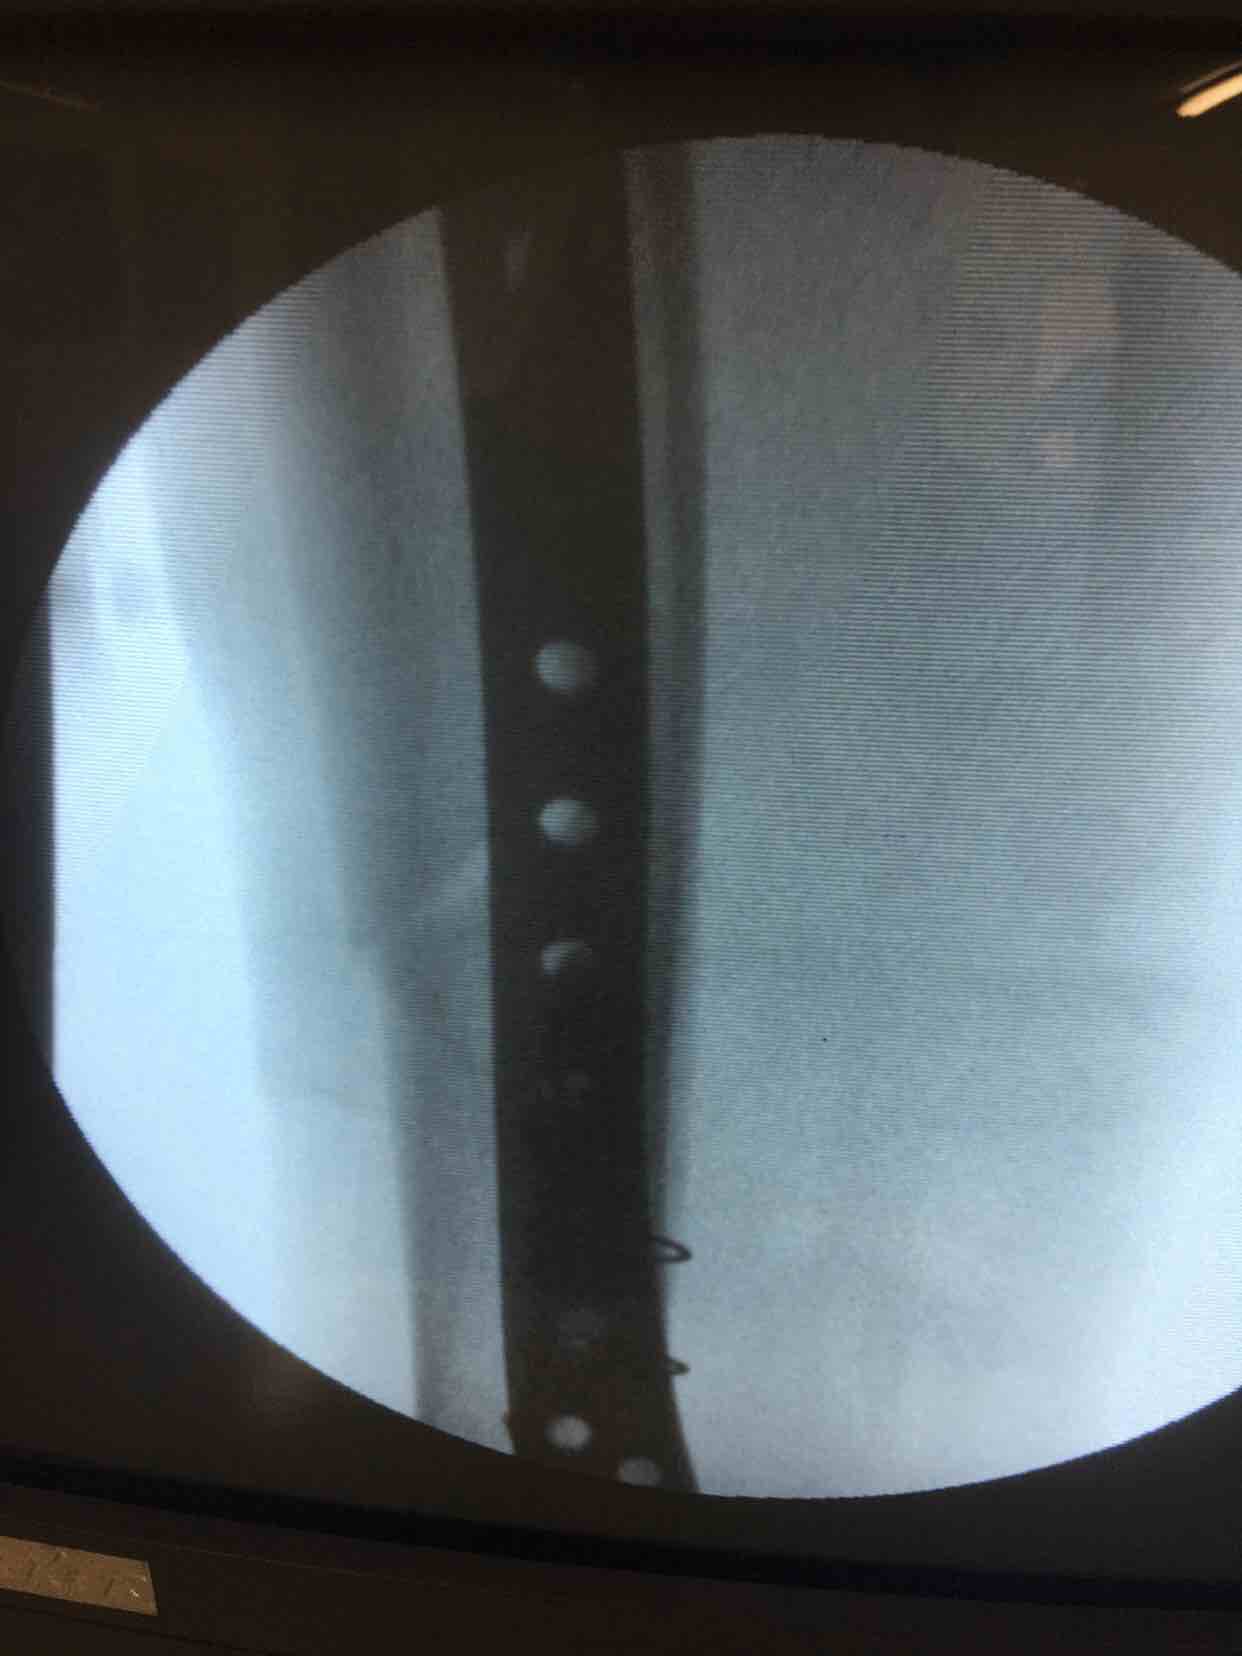

诊断右胫腓骨粉碎性骨折

在腰麻下行切开复位内固定术,术后抗炎,消肿等处理。